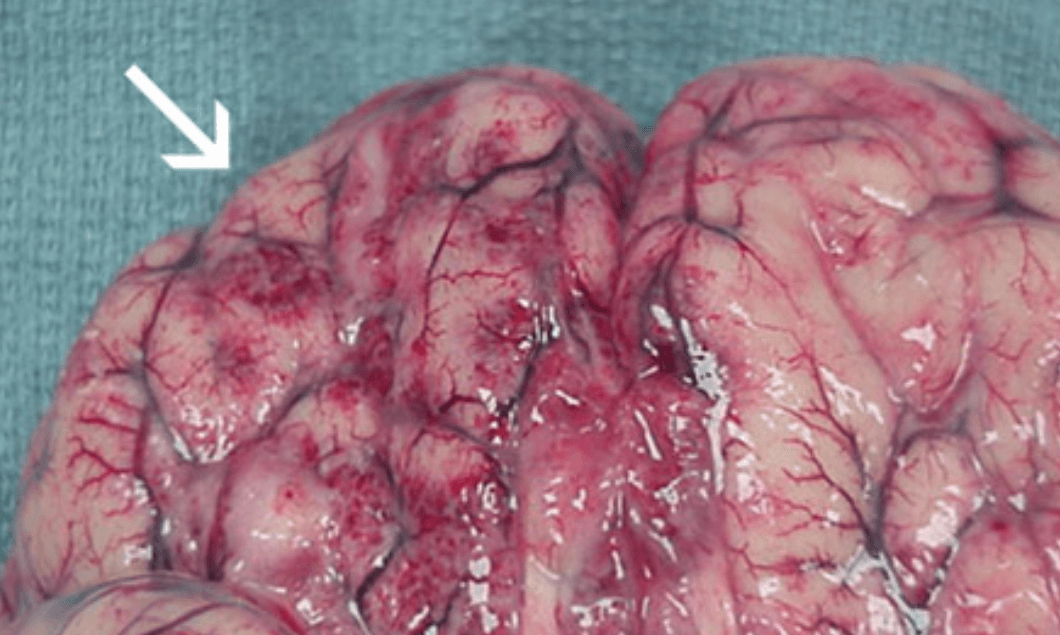

네글레리아 파울러리는 물속에서 사람의 코를 통해 뇌에 침투하면 세포를 파괴하고 심각한 피해를 초래합니다. 1962년부터 2020년까지 확인된 환자 중 151명 가운데 147명이 사망(치사율 97.3%)한 것으로 알려져 있습니다. 이에 따라 보건 당국은 예방을 위해 물 속에서의 안전한 행동과 적절한 위생 수칙을 주의하도록 당부하고 있습니다.